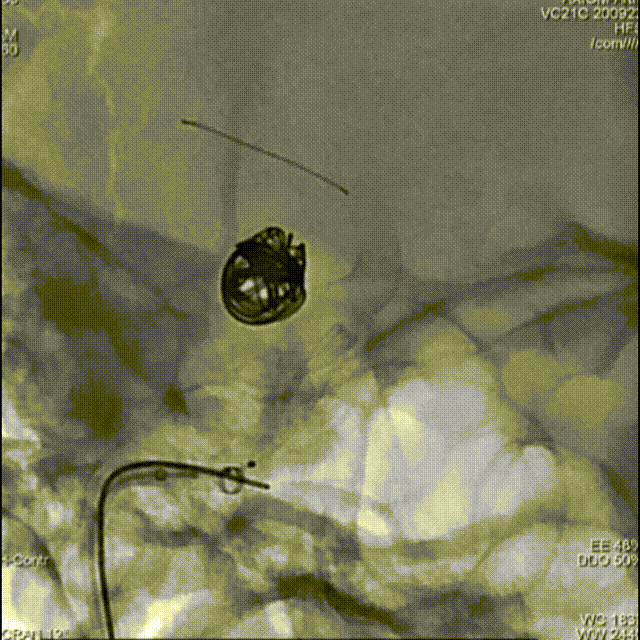

支架导管及弹簧圈微导管先后超选到位,其中弹簧圈微导管超选入远端眼动脉段动脉瘤内备用,根据测量结果,选用YonFlow®血流导向密网支架 4.5mm/30mm、弹簧圈9mm/40cm,先部分推出弹簧圈在动脉瘤内提供保护。再释放密网支架。

1、该病例为串联颈内动脉动脉瘤,符合密网支架应用指征。动脉瘤均位于虹吸段弯曲血管处,跨弯曲的远近段定位不理想时,需要重新回收再释放,对密网支架的操作性能(精准定位、打开贴壁等)有着较高的要求。

2、本例术中应用100%可回收的YonFlow®血流导向密网支架,支架网丝远端头端具有“球头设计”,输送顺滑,可避免管壁损伤,多次回收再释放,帮助术者实现精准定位;其钴铬合金材质网丝可以提供适宜的径向支撑力,又有较好的顺应贴壁表现;创新设计的可控解脱释放方式,可解决目前传统血流导向密网支架临床应用中面临的许多困难,在支架定位、打开贴壁、精准落点、安全性方面带来很大的提升。